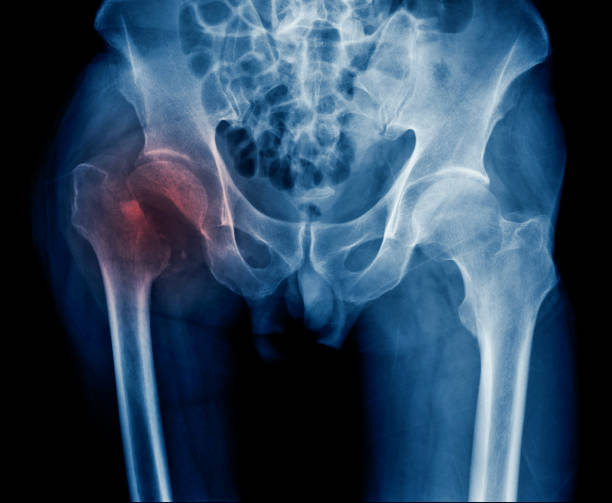

고관절 수술후 회복기간- 수술 후 7주~12주: 운동 및 일상활동의 복귀

7주~12주가 지나면, 조금씩 운동하고 일상활동을 하기 시작할 수 있습니다. 이 때에는 자신의 체력과 회복 상태에 맞게 운동을 시작하고, 일반적인 일상생활에 복귀하면서 천천히 몸의 기능을 복구해 나갑니다. 이 과정에서도 근력 강화와 균형 향상을 위한 운동을 꾸준히 실시해야 합니다.

중요한 점은 회복 기간은 개인의 상태와 수술의 종류에 따라 다르다는 것입니다. 따라서, 의사의 지시에 따라 정확한 회복 기간과 운동 계획을 수행해야 합니다.